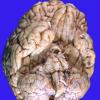

NEOPLASMS (HEMATOLYMPHOID)

Lymphoma, secondary (6)